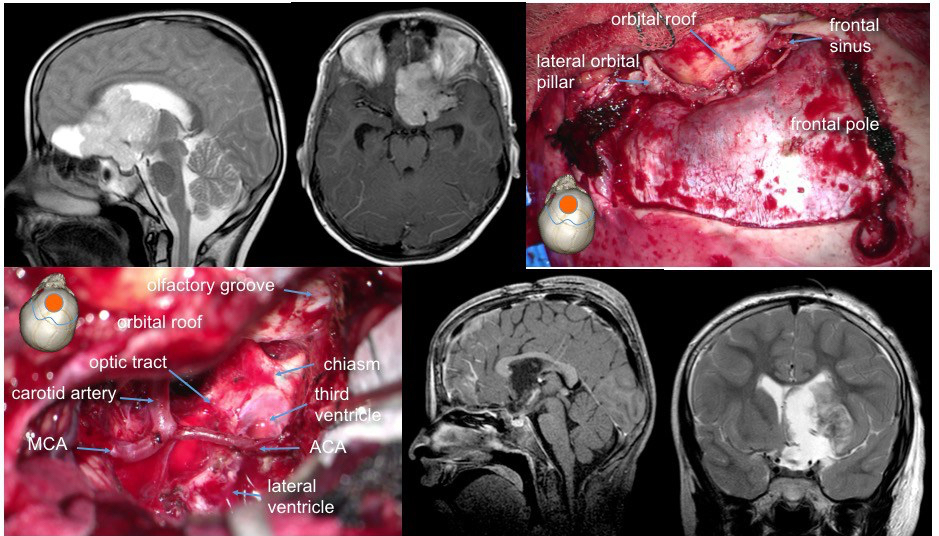

la voie sous-frontale

c’est la plus utilisée dans notre pratique pour les craniopharyngiomes, présentant le grand avantage d’un contrôle médian de toutes les structures, en particulier :

- les deux nerfs optiques

- le nerf olfactif du côté opéré

- les deux carotides

- l’artère cérébrale moyenne du côté opéré

- les deux artères communicantes postérieures

- les deux nerfs oculo-moteurs

- l’artère basilaire

- le contenu sellaire

- la face inférieure de l’hypothalamus

- le troisième ventricule

. elle est cependant limitée :

- vers le haut par le rebord orbitaire, puis la commissure blanche antérieure

- vers le bas par le tubercule de la selle, puis le dorsum sellae

- vers l’arrière par le chiasma

- latéralement par le nerf optique et la carotide puis l’artère communicante postérieure

les régions non contrôlées visuellement sont surtout antérieures :

- le fond de la selle en particulier vers l’avant

- la face interne du sinus caverneux

- la face interne de l’espace opto-carotidien

- l’extension vers la fosse postérieure et l’angle ponto-cérébelleux est limitée par la le dorsum sellae et la veine de Dandy

avantages

il s’agit d’une voie pratiquement médiane, qui permet d’épargner au mieux les axes vasculaires, et de contrôler le contenu sellaire. excellent contrôle direct du tronc basilaire et de ses branches.

inconvénients

la voie sous-frontale est extensive, avec un grand scalp, une dépose du rebord orbitaire et cranialisation du sinus frontal. les régions mal vues sont surtout la face interne du coude antérieur de la carotide et l’espace perforé antérieur.

la préservation du nerf olfactif controlatéral est le plus souvent possible ; la préservation du nerf homo-latéral est est parfois possible, mais sa fonction est sujette à caution, et il faut mettre en balance le bénéfice de conserver un deuxième nerf olfactif (un seul suffit en général) et celui de compromettre la résection tumorale.